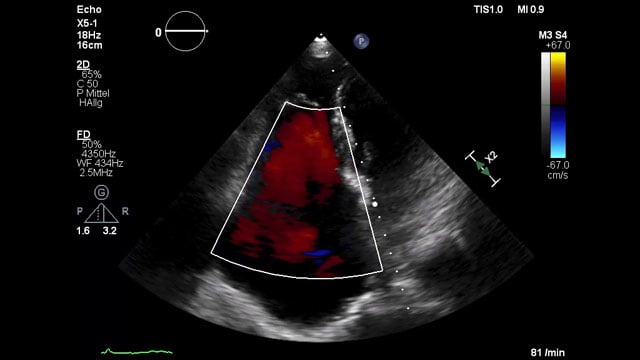

Severe MR in a high-risk patient with a suboptimal anatomy for M-TEER: what other options can we find?

Multimodality imaging reveals fibro-calcific leaflet disease, restricted motion, and a short posterior leaflet, making him a suboptimal candidate for M-TEER and prompting consideration of transcatheter mitral valve replacement. How would you treat?